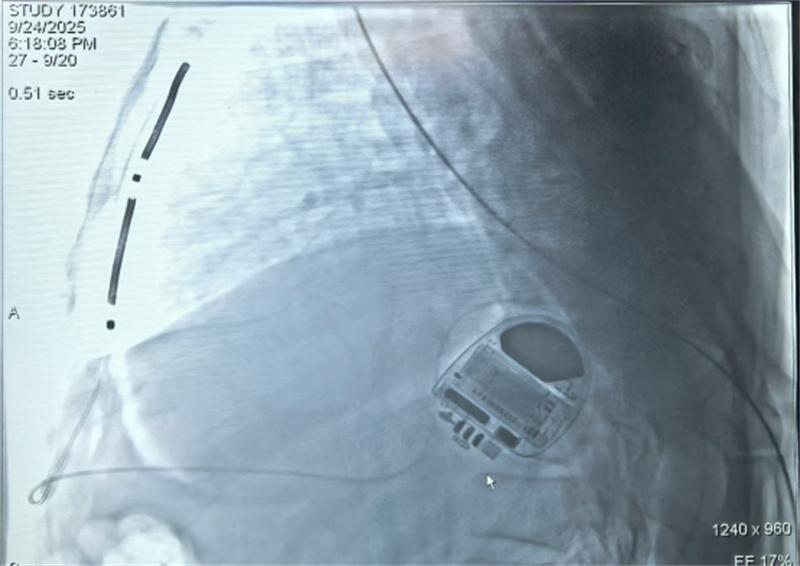

血管外心脏植入式心律除颤转复器。中南大学湘雅二医院供图人民网长沙9月26日电 9月24日,中南大学湘雅二医院心血管内科成功为一名心脏性猝死高危患者实施了湖南省首例血管外植入式心律转复除颤器(EV-ICD)手术,成为全国首批完成该除颤器的植入团队。这不仅是我国心脏植入式除颤治疗领域的新突破,也标志着湖南省在防治心脏性猝死领域器械植入实现多元化。

湘雅二医院心脏电生理团队联合心血管外科教授廖晓波和麻醉科副教授刘镭,多学科协同作战,通过胸骨下方的微小切口,精准放置专用的血管外除颤导线至胸骨后间隙,并连接至左侧腋下除颤器主机,该系统的导线相较于传统经静脉心脏除颤器而言,能够完全避开心脏与血管系统,通过胸骨后贴近心脏的导线,监测与治疗功能。术中测试显示,设备对室性心律失常的识别灵敏度与传统心脏除颤效能完全一致,整个手术历时1个多小时顺利完成,患者安返病房。

手术现场。中南大学湘雅二医院供图